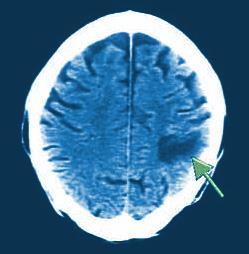

Kada vam frizer pere kosu, ugao vaše glave nad šamponjerom može da izazove štetu na vašim arterijama od hipertenzije. Naime, Elizabet je doživela moždani udar.